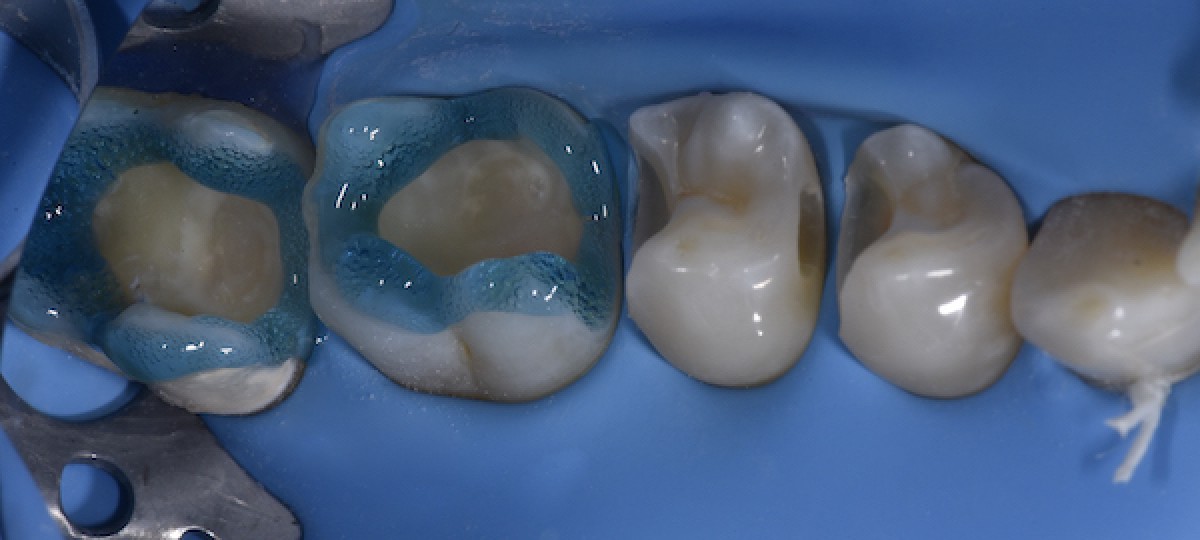

Isolation with rubber dam. Liquid dam was used on 4.7 to ensure a stable seal during the appointment (Fig.2)